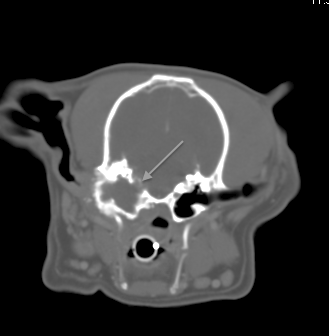

Fig 2:

Transverse CT of the same dog in Fig1 showing erosion into the cranial vault and meningeal enhancement (meningitis)